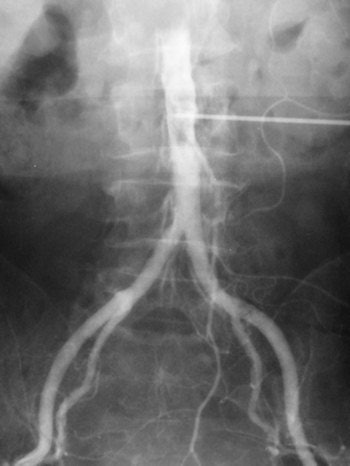

Translumbar aortography

Arteriography was developed in the 1920s with vascular injections from a cutdown. In 1923, Berberich and Hirsch introduced strontium bromide into the femoral artery of a living subject and obtained useful images. The idea was not unreasonable because many cadaveric injections had been made even before 1900. The main problems related to what could be injected and its toxicity.

In Portugal, Egas Moniz made carotid injections in 1927, initially with a cutdown and then by needle puncture. In 1927, building on the experience of Moniz, the team of Reynaldo Dos Santos, Augusto Lamas, and Pereira Caldas from Lisbon described direct abdominal aortic injections. Punctures were made into the aorta with a long needle in a variety of positions, including above the celiac trunk, above the kidneys, above the inferior mesenteric artery, and above the origin of the common iliac artery. The contrast used was a 100% solution of pure sodium iodide that was quite toxic. The injection was painful and therefore required anesthesia.

The translumbar aortogram became the standard vascular examination for decades and was routinely performed at Hammersmith Hospital in London when I started there as a radiology registrar in 1981, more than 50 years after the procedure was first described. There were surprisingly few complications from the procedure. The examination illustrated below was one I performed in 1982.

Translumbar arteriography was replaced by catheter angiography from either the femoral or brachial/radial route. Now diagnostic angiography has been superseded by noninvasive imaging such as Doppler ultrasound and also CT and MR angiography. Angiography is now reserved for access for interventional procedures.